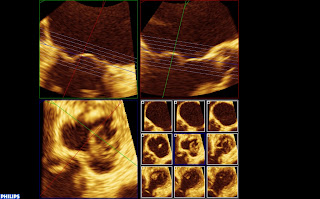

Vue 3D dite « chirurgicale », aorte en haut, auricule au gauche de l’écran, grande valve en haut avec un prolapsus médian et petite valve en bas :

Mitrale 3D from fish Nip echocardiographie on Vimeo.

Enfin, on note une dilatation et surtout une déformation importante de l’anneau (donc plutôt un type 1), qui est quasiment rond. Sur cette reconstruction tridimensionnelle de l’anneau en télésystole, les zones de restrictions paraissent en bleues, la zone prolabant (A2) est jaune. l’aorte est en haut, AL est la commissure antero-latérale.

Sur cette reconstruction 3D, on peut voir, dans le cadre en bas à droite, le petit carré bleu qui correspond au plan de l’anneau. Seul le A2 est au plan de l’anneau, le reste des feuillets sont en dessous, confirmant la restriction.